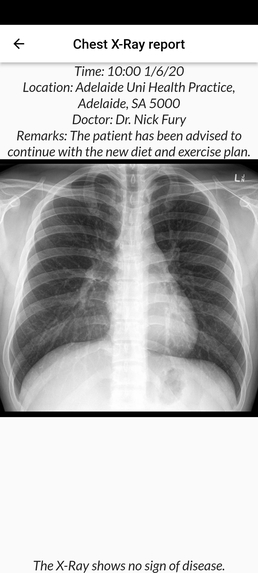

- MEDBUDDY will accompany and support you with all the complicated steps of storing and sharing medical records with just a quick QR scan.